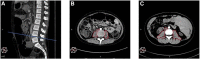

Sarcopenia is a clinical condition characterized by a reduction in muscle mass, which typically affects adult patients; however, it has recently been recognized in pediatric literature. Few studies in children with chronic liver disease (CLD) undergoing liver transplantation (LT) have investigated the role of sarcopenia, with controversial results. The aim of our study was to assess the prevalence and impact of sarcopenia among children with CLD who are candidates for LT. We conducted a retrospective, single-center study at Bambino Gesù Children's Hospital (Rome, Italy) from July 2016 to July 2021, evaluating all children (0-16 years old) with CLD listed for LT with an abdomen computed tomography imaging available before LT. The total psoas muscle surface area (t-PMSA) was defined as the sum of left and right psoas muscle surface area measured at L4-L5 on axial images. The t-PMSA z-score was calculated according to reference data, and sarcopenia was defined as a t-PMSA z-score of ≤-2 (1-16 years) or a psoas muscle index [PMI; PMI = t-PMSA/(100 × BSA)] of <50th percentile of the population examined (<1 year). Clinical, laboratory, and LT outcome data were collected from all the patients with CLD. 27 out 48 (56%) of the patients aged 1-16 years were sarcopenic. No differences were noted in anthropometrics, nutritional support, liver function tests, model for ESLD (MELD), or pediatric ESLD (PELD) scores between patients with and without sarcopenia. The former showed a higher prevalence of respiratory complications (66.7% vs. 42.1%) and need for inotropes (40.7% vs. 10.8%) after LT. Among patients aged 0-1 years (n: 36), those with reduced muscle mass (50%) had a longer hospitalization time (44 vs. 24 days) and higher incidences of multi-organ failure syndrome (38.9% vs. 0%) and intensive care unit-related infections (61.1% vs. 27.8%) compared to those with greater muscle mass. t-PMSA and PMI were statistically significant predictors of LT outcomes. Sarcopenia is a reliable index of frailty in children with CLD, as its presence is associated with the risk of a more challenging LT. Future studies will have to investigate the functional aspects of sarcopenia and conceive preventive measures of muscle wasting in CLD patients.